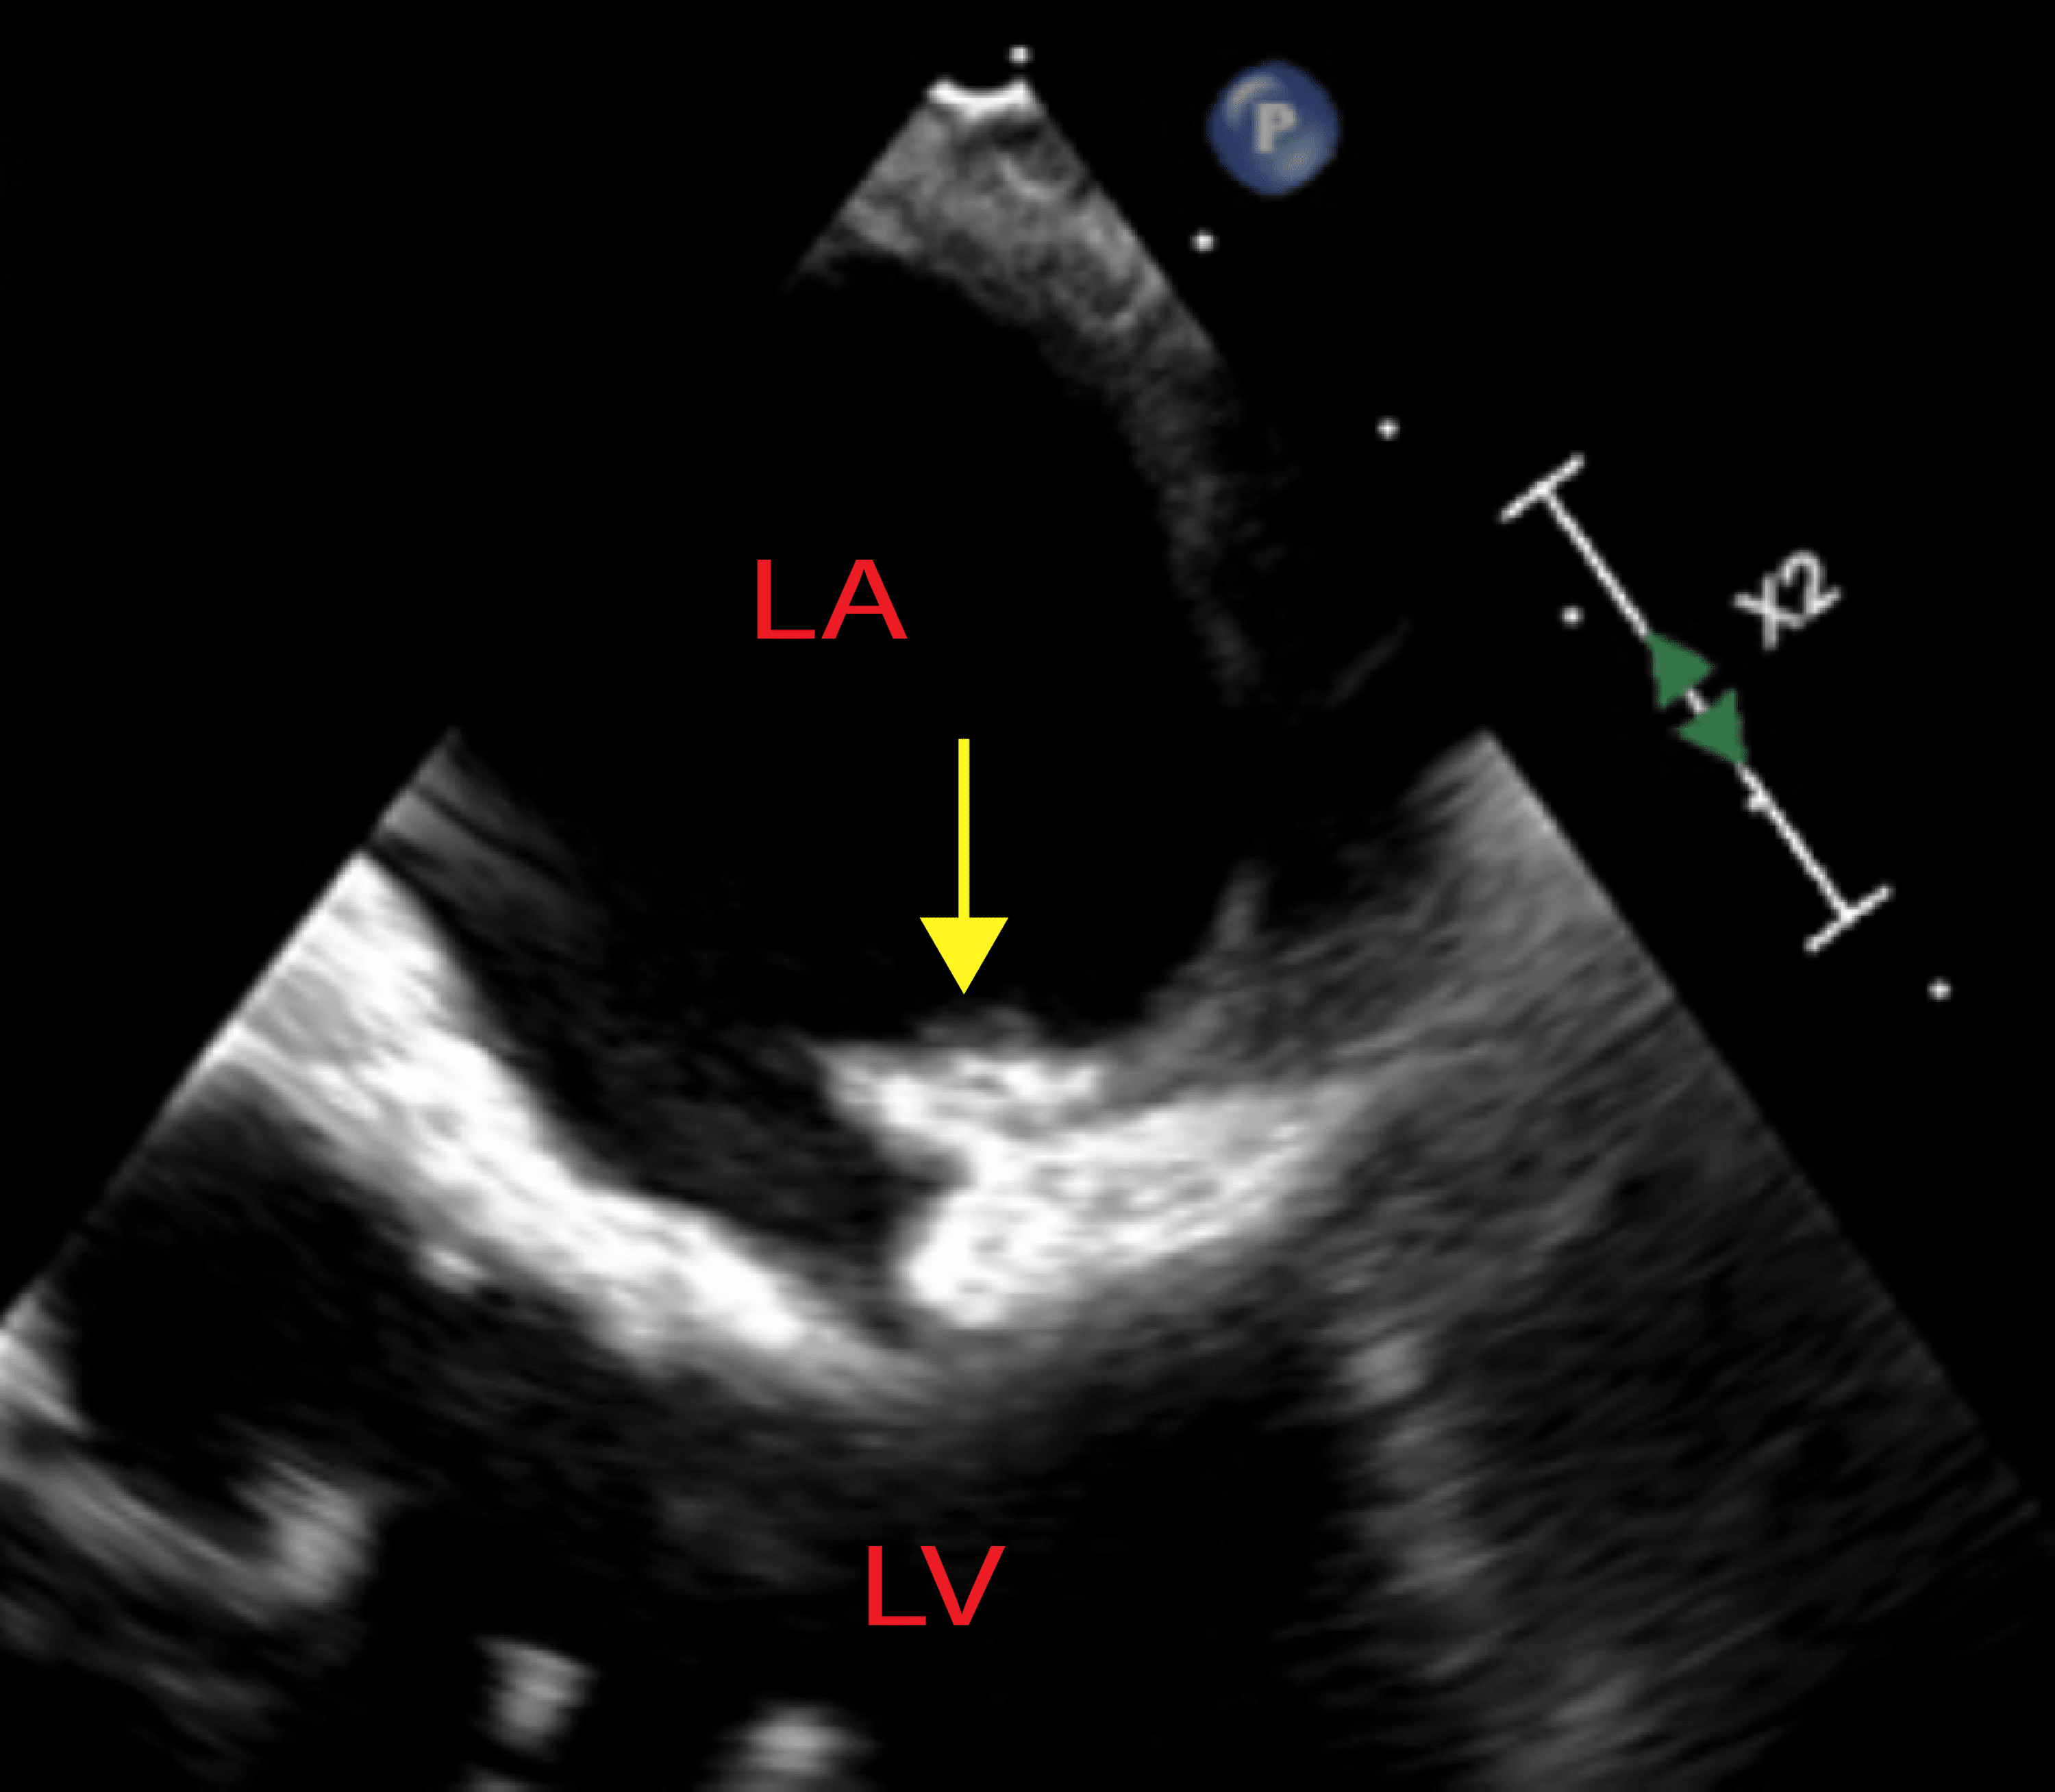

Viridans streptococcal (Streptococcus intermedius) mitral valve Strep Heart Valve Disease — rheumatic heart disease is a condition with heart valve damage from rheumatic fever. — rheumatic heart disease is a serious complication of group a streptococcus infection. — the disease results from damage to heart valves caused by one or several episodes of rheumatic fever, an. This lining is called the. — infective endocarditis (ie), also. Strep Heart Valve Disease.

Cureus Commensal Streptococcal Infective Endocarditis of the Native Strep Heart Valve Disease — rheumatic heart disease is a systemic immune condition that occurs as a complication of rheumatic fever. This can happen after an. — rheumatic heart disease is a serious complication of group a streptococcus infection. This lining is called the. — the disease results from damage to heart valves caused by one or several episodes of rheumatic. Strep Heart Valve Disease.